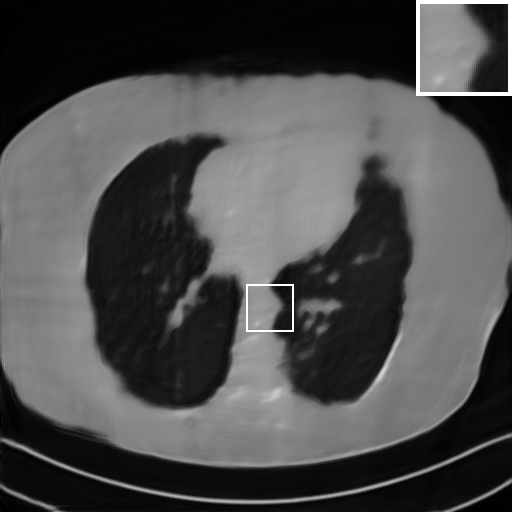

Fig. 7 manifests the reconstruction results of these methods with scanning angular of . It can be seen that both FBP and FBP-Unet produce serious artifacts within the range of missing angles. The TV model performs well in removing Poisson noises, but it can not handle the artifacts very well. Similarly, there left obvious artifacts on boundaries and different degrees of missing in visceral tissues of the reconstruction images obtained by the SIPID, PD-net and FSR-net. The visceral tissue and boundaries of our LRIP-net reconstructions are more intact and smoother, especially for the LRIP-net1/8 which gives the ideal boundaries. The observation becomes even apparent if we look at the zoom-in regions, where the LRIP-nets can produce results with fine structures. Therefore, we conclude that the low-resolution image prior can effectively improve the qualities of the limited-angle CT reconstruction.